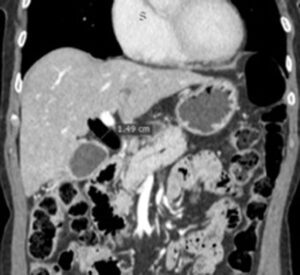

Из анамнеза известно, что пациентка в августе с диагнозом «механическая желтуха» в порядке скорой помощи госпитализирована в клинику госпитальной хирургии. В ходе обследования при фиброгастродуоденоскопии определяется опухоль большого дуоденального сосочка, выполнена биопсия. При выполнении МРТ и КТ (рис. 1) определяется расширение внутрипеченочных и внепеченочных желчных протоков, вирсунгэктазия, отдаленных метастазов не выявлено.

Рисунок – 1. А: МРТ органов брюшной полости: определяются признаки билиарной и панкреатической гипертензии опухолевого генеза; Б: КТ-ангиография живота: признаки билиарной гипертензии (расширение гепатикохоледоха до 1,49мм).